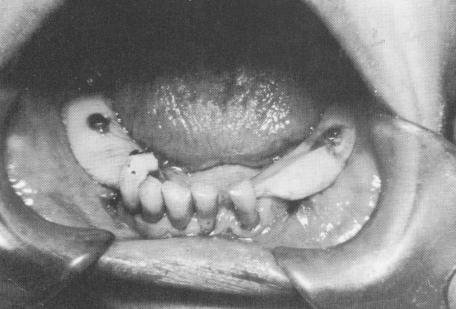

Fig. 7-52. Intraoral bandages may be used to protect wounds of the soft tissue.

1 Bandages protect soft tissues around subperiosteal implants